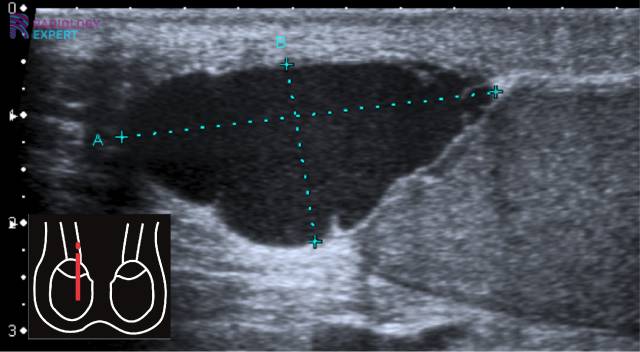

Op een echo kan een tumor er anders uitzien dan een cyste. Vaak heeft hij een onregelmatige vorm, vastere structuur en soms ook bloedvaten eromheen. Maar eerlijk is eerlijk, op een echo is het niet altijd 100% zeker te zeggen of iets goedaardig of kwaadaardig is.

De Echo: Een eerste indruk

De echo is dus een belangrijk hulpmiddel om een eerste indruk te krijgen van wat er zich in je lichaam afspeelt. Het kan een cyste of een tumor opsporen, maar het kan niet altijd met zekerheid zeggen wat het precies is. Zie het als een selfie die je maakt: je ziet jezelf, maar je innerlijk kun je er niet mee vangen.